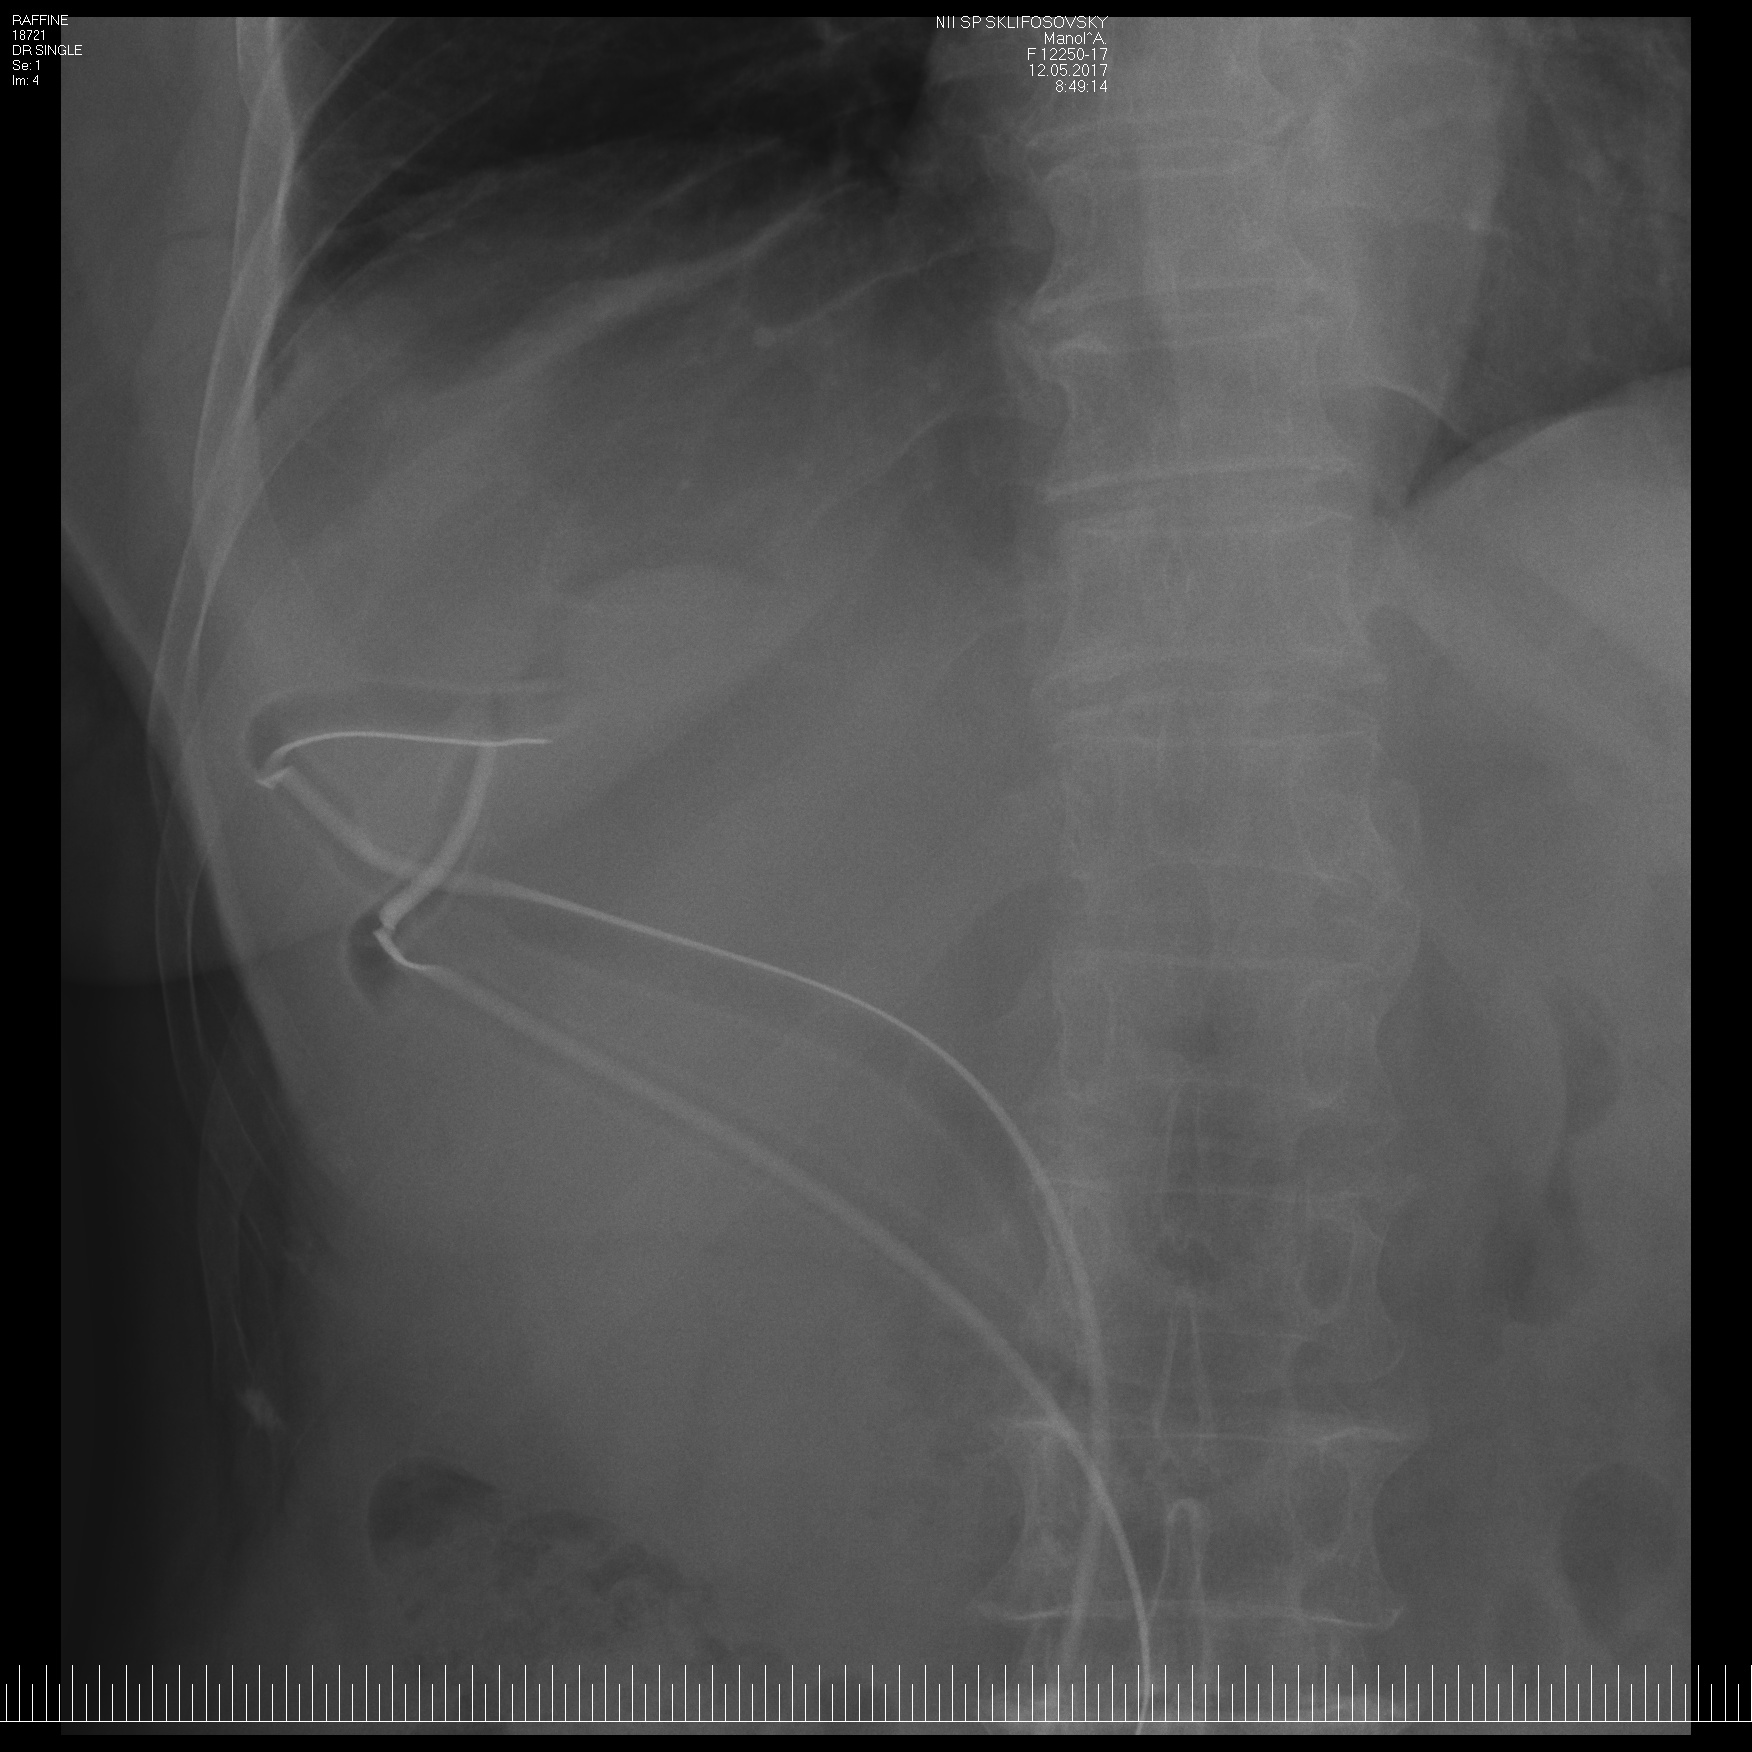

Несмотря на примесь желчи в содержимом кисты, при рентгеновской фистулографии

желчные протоки не контрастировались:

Пациентка провела у нас 15 дней и выписана с двумя трубками с очищенной полостью на заживление и амбулаторном наблюдении по разработанному алгоритму.

| | |

| Обзорный снимок - 3 трубки | Фистулография - полость сократилась, оболочек нет, в желчные протоки контраст не попадает | Трубка 12Fr удалена, трубки 24Fr - скорректированы. |